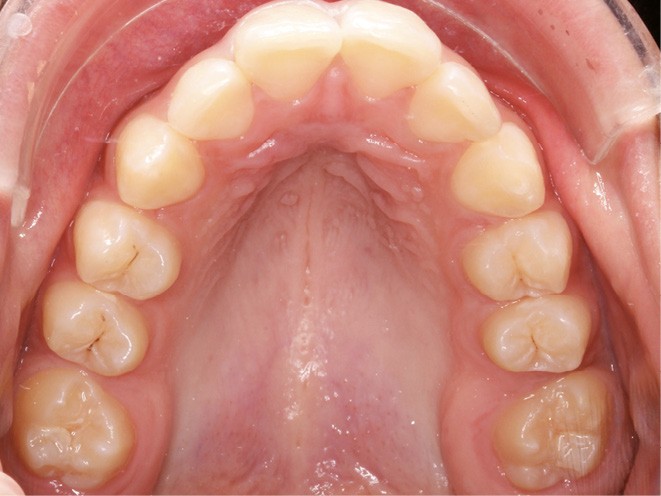

Examen endobuccal (fig. 2a-e)

L’hygiène est satisfaisante et le parodonte sain. On note aux deux arcades l’absence des premières molaires et la fermeture partielle des espaces d’extraction avec mésiorotation marquée de 17, 27 et 37. À la mandibule, l’encombrement antérieur est estimé à 2 mm et les espaces d’extraction résiduels à 12 mm.

Dans le sens transversal, malgré une occlusion correcte des secteurs latéraux, on observe une endoalvéolie maxillaire et une non-concordance des médianes incisives avec déviation de la médiane mandibulaire vers la droite. Le recouvrement incisif est normal.